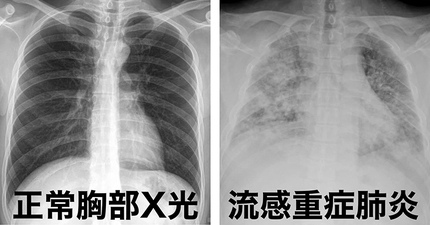

怎麼肺炎人就走了?胸腔醫示警6症狀快送醫「死亡率高達40%」

大S病逝「死於重症大白肺」 醫白話解釋:被痰活活淹死